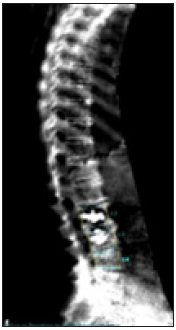

Patient C began osteological therapy at the age of 55 in 2000 with colleagues who had previously treated her. Initially adjusted to weekly oral bisphosphonates, the patient received prolia injections for a compliance disorder from 2013-2016. After a control DXA measurement (T-score femoral neck right -2.86SD), DMAB was discontinued without specific follow-up therapy because of "good improvement in values and low osteoporosis". After discontinuation, three new WK fractures (LWK2,3,4) occurred in the course of the year, of which LWK2 and LWK3 were kyphoplasted (Figure 13). The patient then suffered a fracture of the radius on the right and fractures of the carpal bones on the right, several fractures of the fingers and toes.

Figure 13: